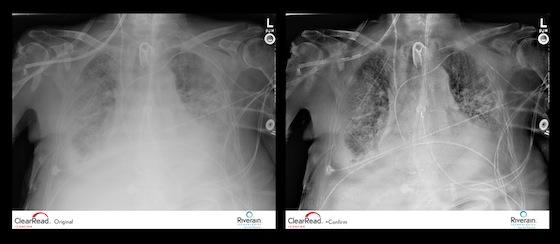

ClearRead +Confirm greatly increases the readability of portable chest X-rays by selectively increasing contrast and suppressing the clavicles and ribs in the image, thus removing obstacles that could be obscuring the visibility of feeding, drug delivery and pain management tubes, lines and cardiac wires.

Portable chest X-ray machines are routinely used to confirm the placement of lines and tubes; however, the quality of the image from a portable machine can make it challenging to see the devices. Chest X-rays on portable machines often need to be adjusted to make the edges and tips of the devices stand out, which is time consuming for radiologists.